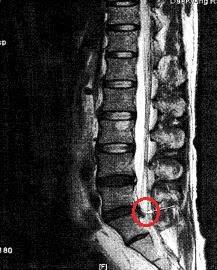

또 하나는 추간판이 어느 쪽으로 탈출되었는지를 판독해야 하는데 그 기준은 아래 그림과 같습니다. 탈출 부위에 따라 예상되는 증상이 달라집니다.

postero는 뒤쪽이란 의미이고 lateral은 바깥쪽이란 의미입니다.

Line a는 시상면의 중앙이고, line b는 후관절 관절면의 가장 안쪽 면을 통과하는 line a와 평행한 선이며, line c는 line a와 c의 중앙을 지나는 평행선이다. Lateral은 탈출된 추간판의 첨부가 line b를 지나는 경우, lateral postero-lateral은 탈출된 추간판의 첨부가 line b와 c 사이를 지나는 경우, central postero-lateral은 탈출된 추간판의 첨부가 line a와 c 사이를 지나는 경우, central은 탈출된 추간판 첨부가 line a를 지나는 경우를 각각 말한다.